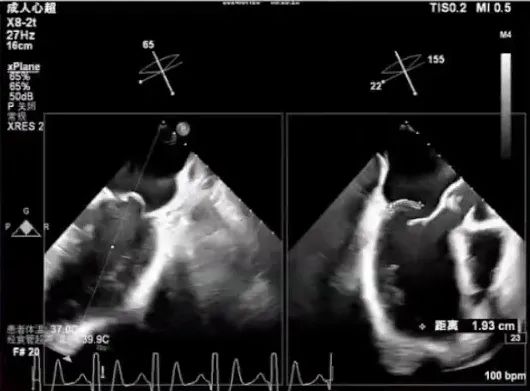

经食道超声检查

经食道检查结果显示,1区瓣叶结构良好,主要脱垂集中于P2区,3区未见明显受累。

进一步评估患者病变情况,前叶长度2.74mm,后叶长度1.93mm;房间隔前后径4.0cm,房间隔长径6.9cm,瓣口面积6.27cm²,平均跨瓣压差5mmHg。

AML length(A2):2.74mm

PML length(P2):1.93mm

Fail gap:9mm

Fail width:19.2mm

房间隔前后径:4.0cm

房间隔长径:6.9cm

MVA:6.27CM²

PG:5mmHg